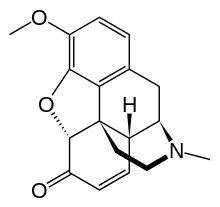

Structures

| Morphides | ||||

|---|---|---|---|---|

Codeine Codeine |

Morphine Morphine |

Oripavine Oripavine |

Pseudomorphine Pseudomorphine |

Thebaine Thebaine |